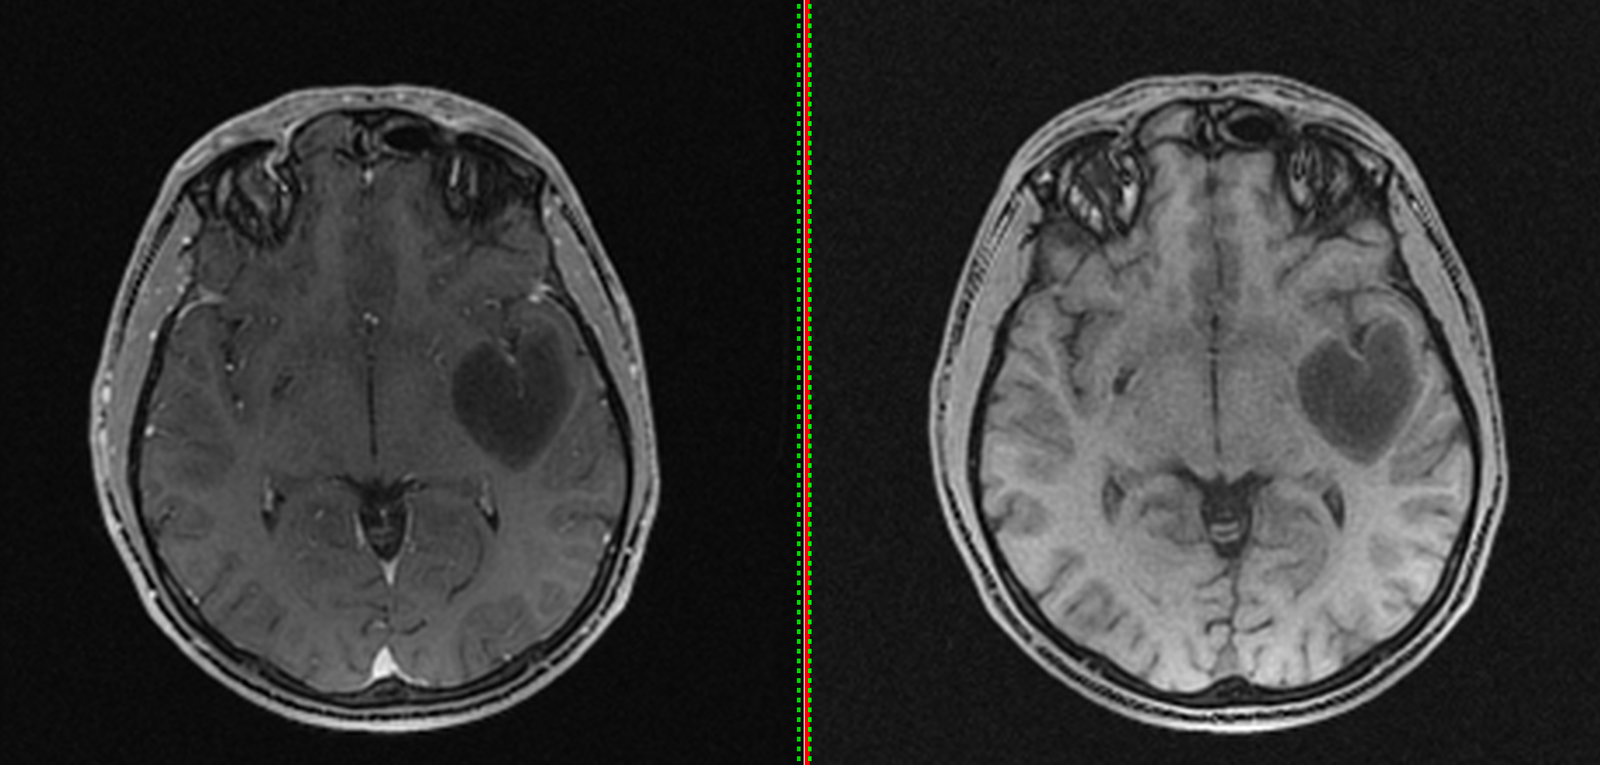

Tumora era bine delimitată, cu priză omogenă de contrast, și are origine din dura mater (foița externă a meningelui) de la nivelul șanțurilor olfactive – porțiunea din baza craniului pe unde trec nervii olfactivi. Aspectul RMN sugerează un diagnostic histopatologic de meningiom – tumoră benignă (în peste 95% din cazuri) .

RMN cerebral de control efectuat a doua zi după operație confirmă rezecția completă a tumorii și absența oricăror complicații.